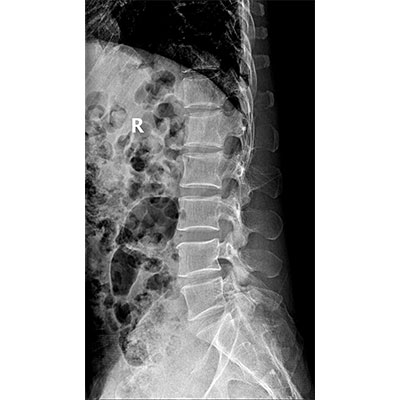

● 采用自主研發(fā)的技術(shù),在保證優(yōu)質(zhì)圖像的前提下,大大降低X射線劑量,用心呵護(hù)醫(yī)護(hù)工作者及患者的健康。

● 短曝光時間,便于老年人、兒童、殘疾人進(jìn)行臨床拍攝。避免這類群體因不能有效控制身體運(yùn)動等因素造成的運(yùn)動偽影,提高攝片質(zhì)量及效率。